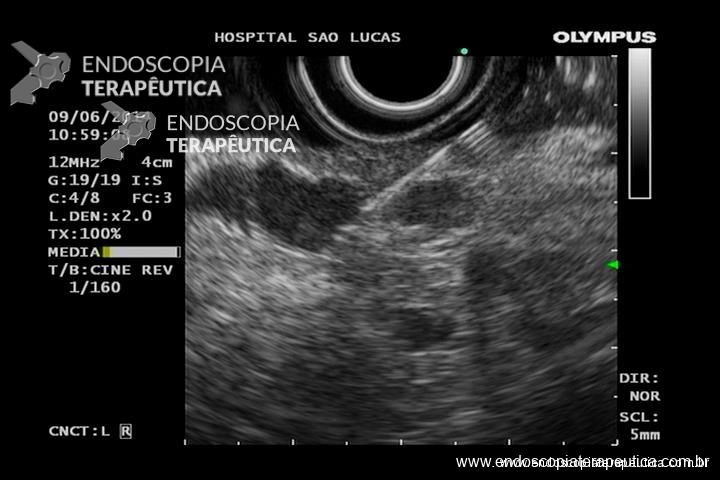

GIST gástrico